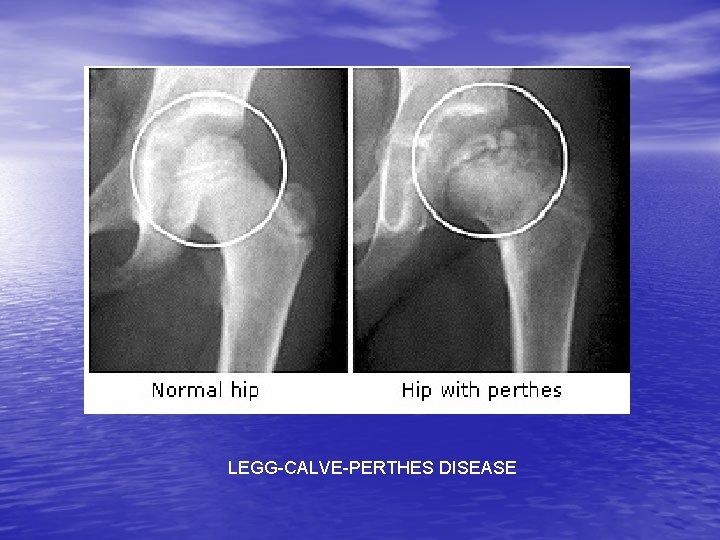

HIP, GROIN AND PELVIC INJURIES • Groin strain: muscle(s) strains • Trochanter Bursitis: inflam of burseas • Sprains of the hip joint • Dislocated hip joint: Greater trochanter out of • • • acetabulum Avascular Necrosis: loss of blood flow Legg-Calve-Perthes Disease (coxa plana) Snapping Hip Phenomenon: instablility of ligaments in the hip

LEGG-CALVE-PERTHES DISEASE